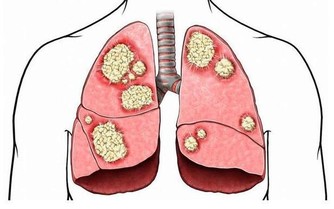

阿爾茨海默病是種常見的老年癡呆症,患這種病早期有哪些症狀?發展到後期會有哪些後果?今天為大家介紹清楚。

醫生提醒:出現這些症狀離老年癡呆不遠了! 最壞的結果是什麼?